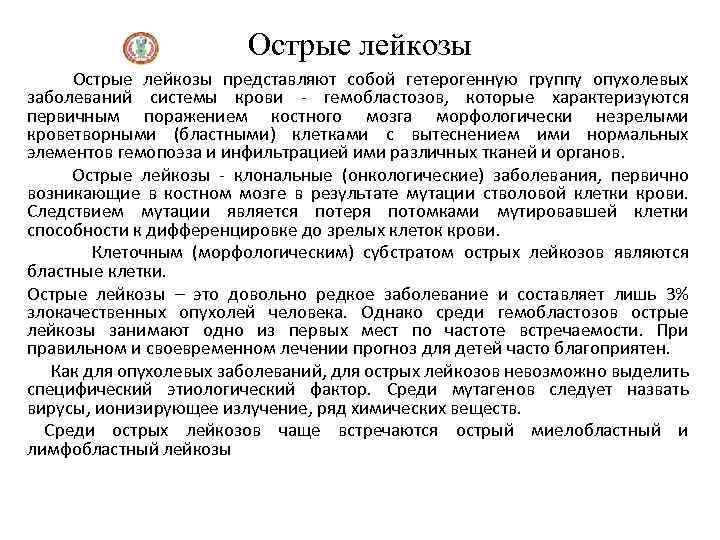

Острые лейкозы Острые лейкозы представляют собой гетерогенную группу опухолевых заболеваний системы крови - гемобластозов, которые характеризуются первичным поражением костного мозга морфологически незрелыми кроветворными (бластными) клетками с вытеснением ими нормальных элементов гемопоэза и инфильтрацией ими различных тканей и органов. Острые лейкозы - клональные (онкологические) заболевания, первично возникающие в костном мозге в результате мутации стволовой клетки крови. Следствием мутации является потеря потомками мутировавшей клетки способности к дифференцировке до зрелых клеток крови. Клеточным (морфологическим) субстратом острых лейкозов являются бластные клетки. Острые лейкозы – это довольно редкое заболевание и составляет лишь 3% злокачественных опухолей человека. Однако среди гемобластозов острые лейкозы занимают одно из первых мест по частоте встречаемости. При правильном и своевременном лечении прогноз для детей часто благоприятен. Как для опухолевых заболеваний, для острых лейкозов невозможно выделить специфический этиологический фактор. Среди мутагенов следует назвать вирусы, ионизирующее излучение, ряд химических веществ. Среди острых лейкозов чаще встречаются острый миелобластный и лимфобластный лейкозы